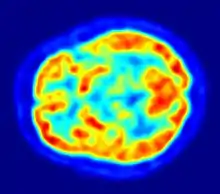

Tehnicile neuroradiologice moderne (Neuroimagistică) permit vizualizarea proceselor neuronale sau metabolice din creier în timpul diverselor activități spontane sau provocate. Deja, începând cu anul 1920, dezvoltarea unor metode electrofiziologice, în primul rând a electroencefalografiei (EEG) de către Hans Berger, a putut pune în evidență modificările electrice produse în creier, în stare normală sau patologicică. În neuroștiința cognitivă actuală se utilizează în special rezonanța magnetică nucleară funcțională (fMRI) și [[Tomografie cu emisiune de pozitroni|tomografia cu emisiune de pozitroni (PET). Cu ajutorul rezonanței magnetice funcționale se pot măsura activitățile cerebrale cu un înalt grad de rezoluție temporo-spațială, în timp ce tomografia cu emisiune de positroni permite punerea în evidență a modificărilor metabolice (consumul regional de oxigen sau de glucoză) în repaus precum și în timpul unor activități motorii sau cognitive. Aceste tehnici implică o serie de probleme etice, când se stabilesc relații neuronale cu modificări ale stării de conștiință.